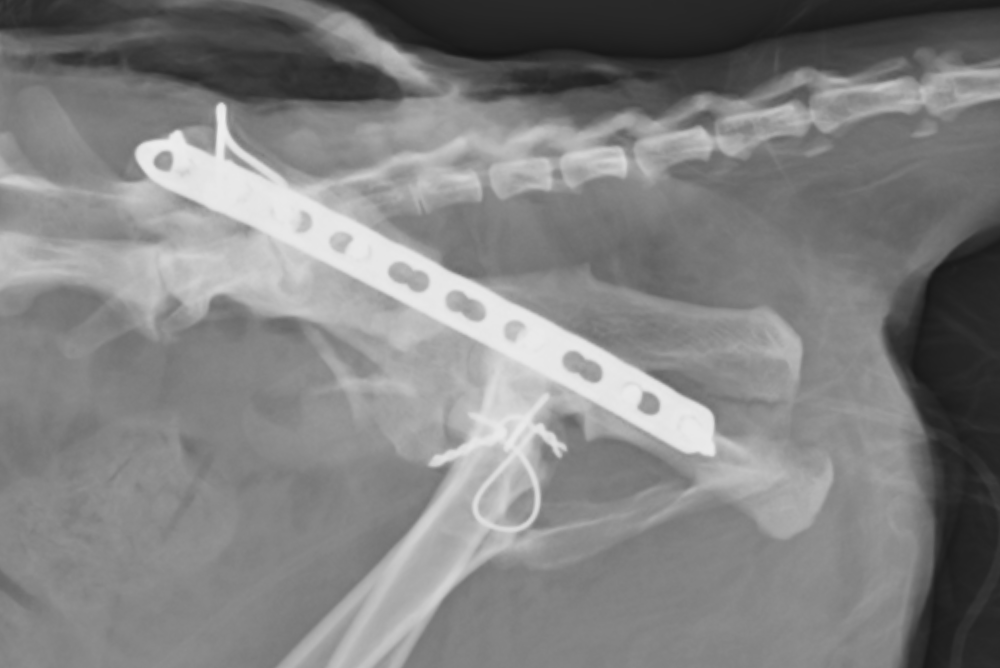

術後のX線です。そもそもが粉砕骨折で完全な整復は困難であり、ロッキングプレートと呼ばれるプレートを用いて、架橋プレートを実施しました。

横から見たレントゲンです。骨盤の広さも重要で、あまりに狭くなってしまっている場合には排便困難となり便秘となってしまうため注意が必要です。今回、骨盤腔はしっかりと確保できているため、問題ありませんでした。